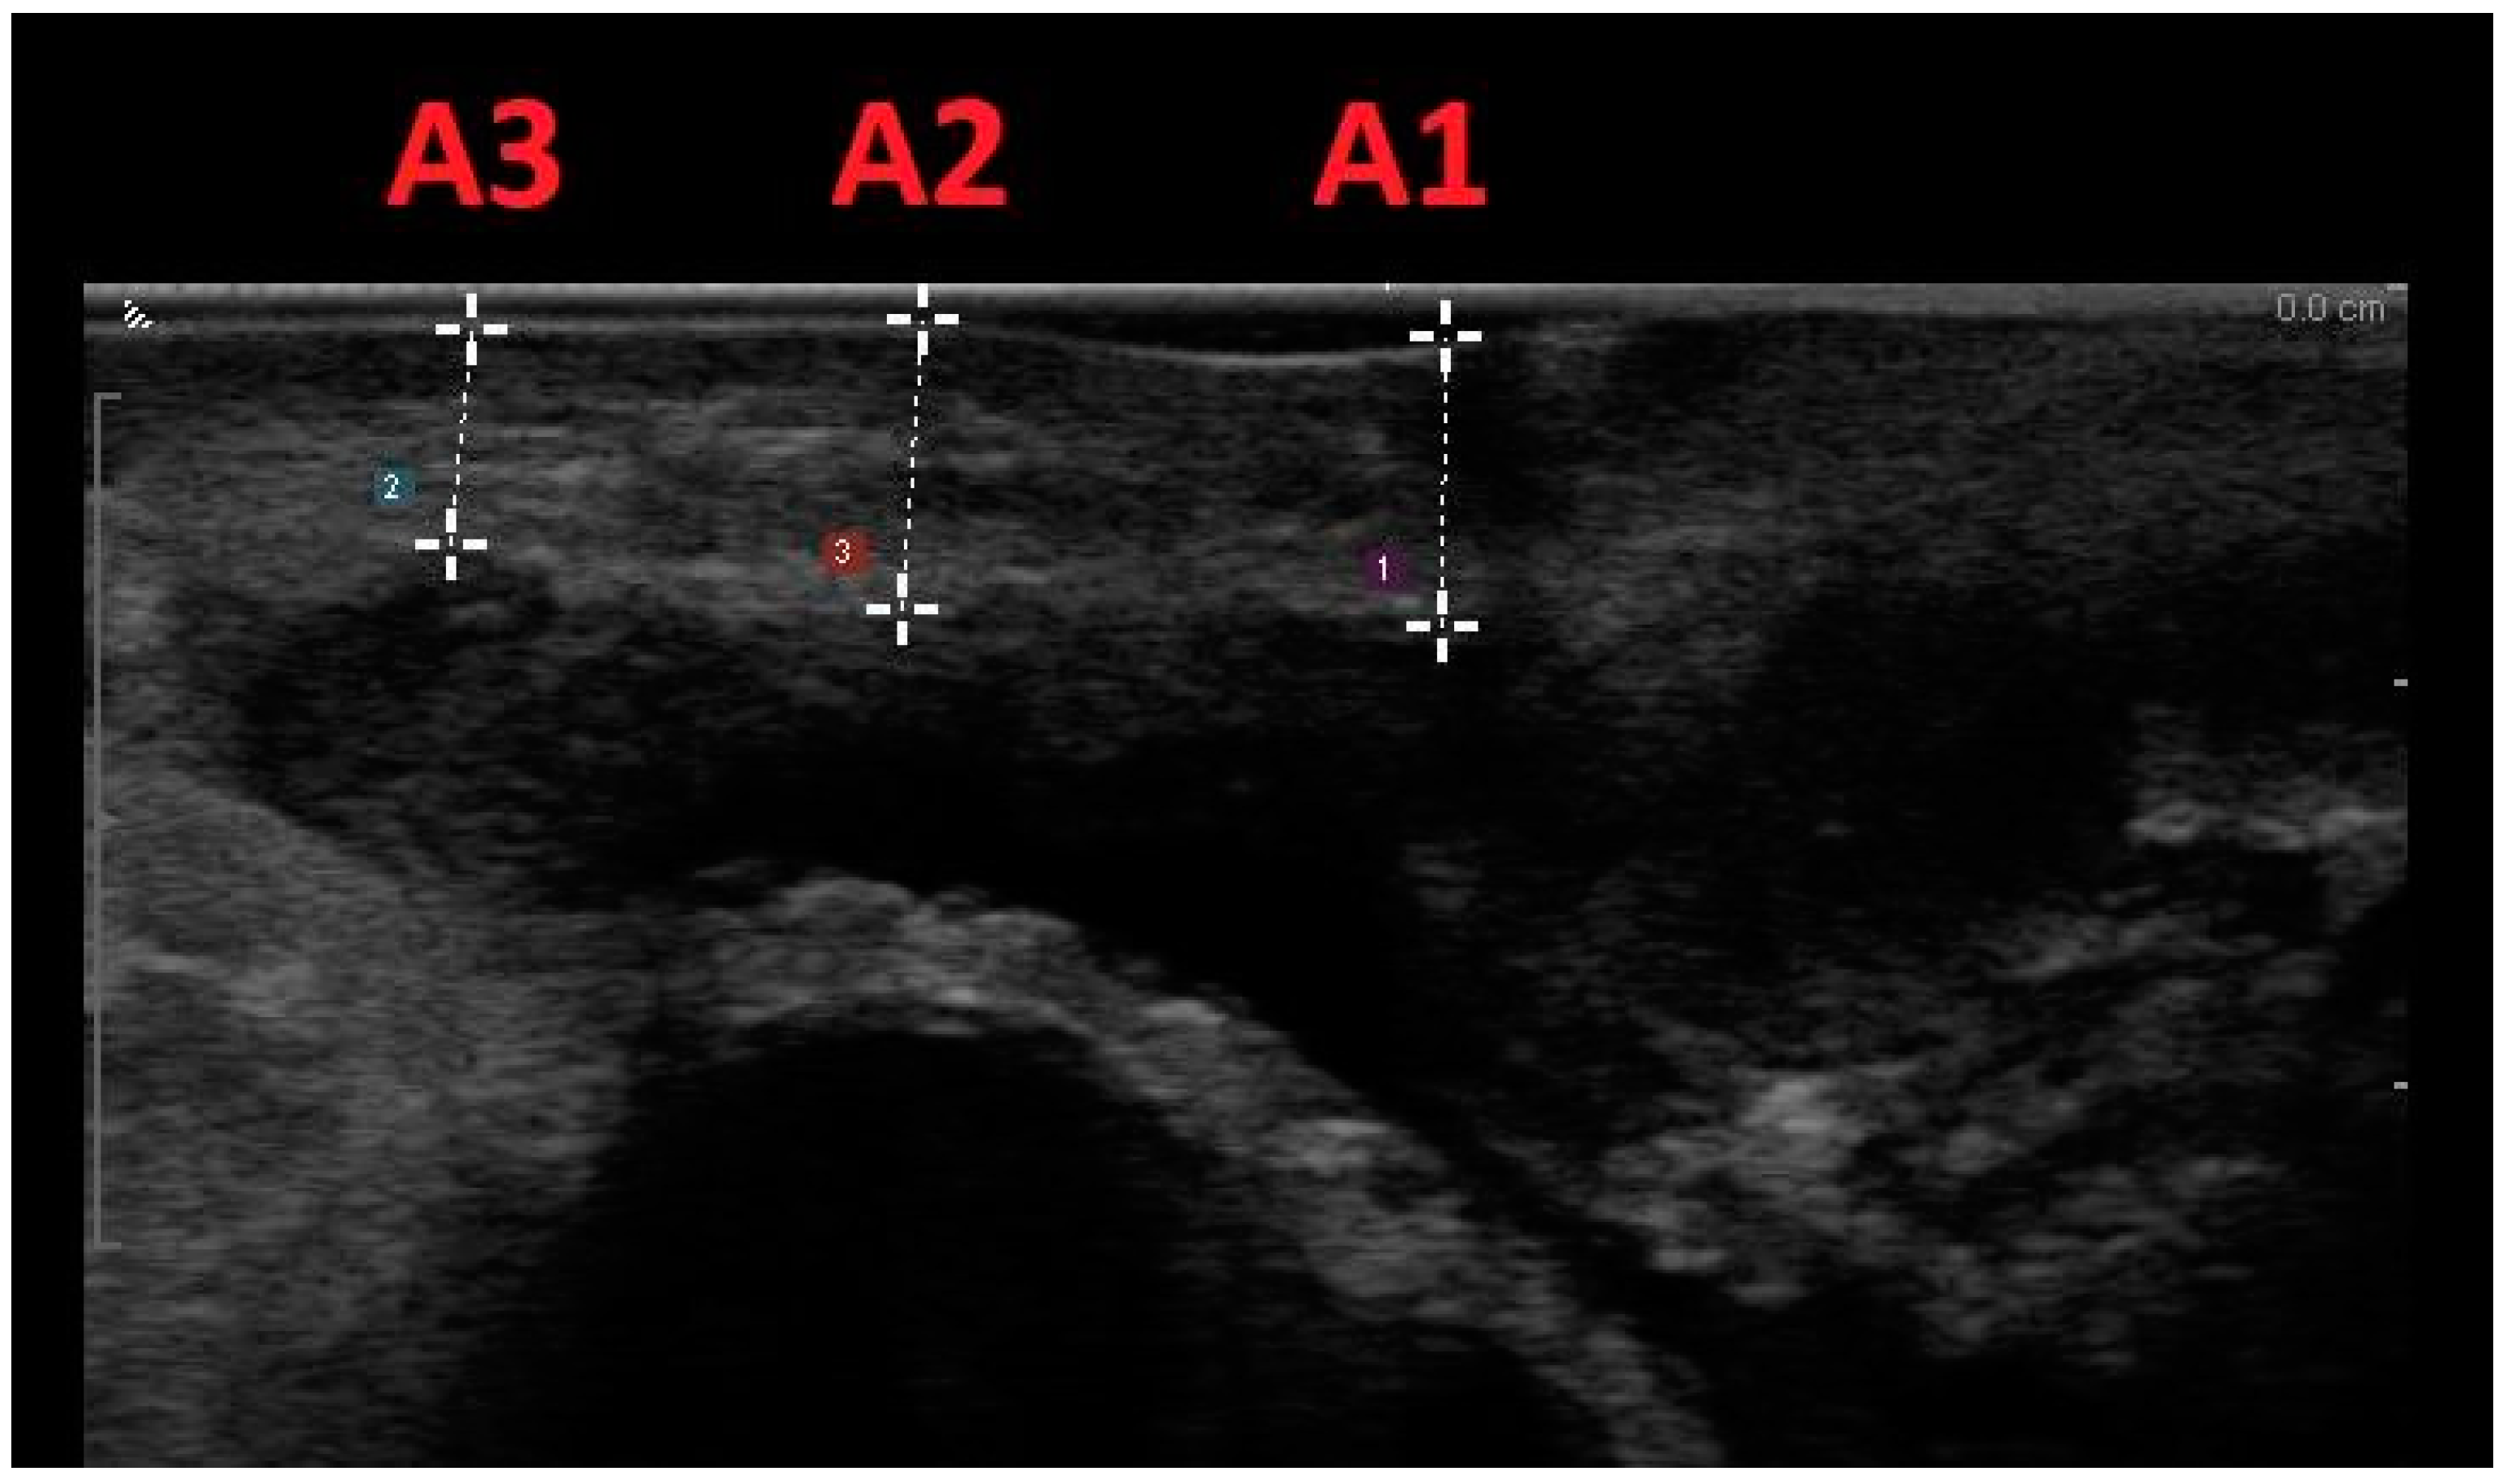

| A1 | 2.8 (1.49) | 3.0 (1.08) | −0.16 | 0.18 | −0.56/0.23 | 0.945 |

| A2 | 2.7 (1.64) | 2.8 (1.42) | 0.05 | 0.1 | −0.17/0.27 | 0.987 |

| A3 | 2.7 (1.39) | 2.7 (1.29) | 0.08 | 0.15 | −0.26/0.42 | 0.931 |